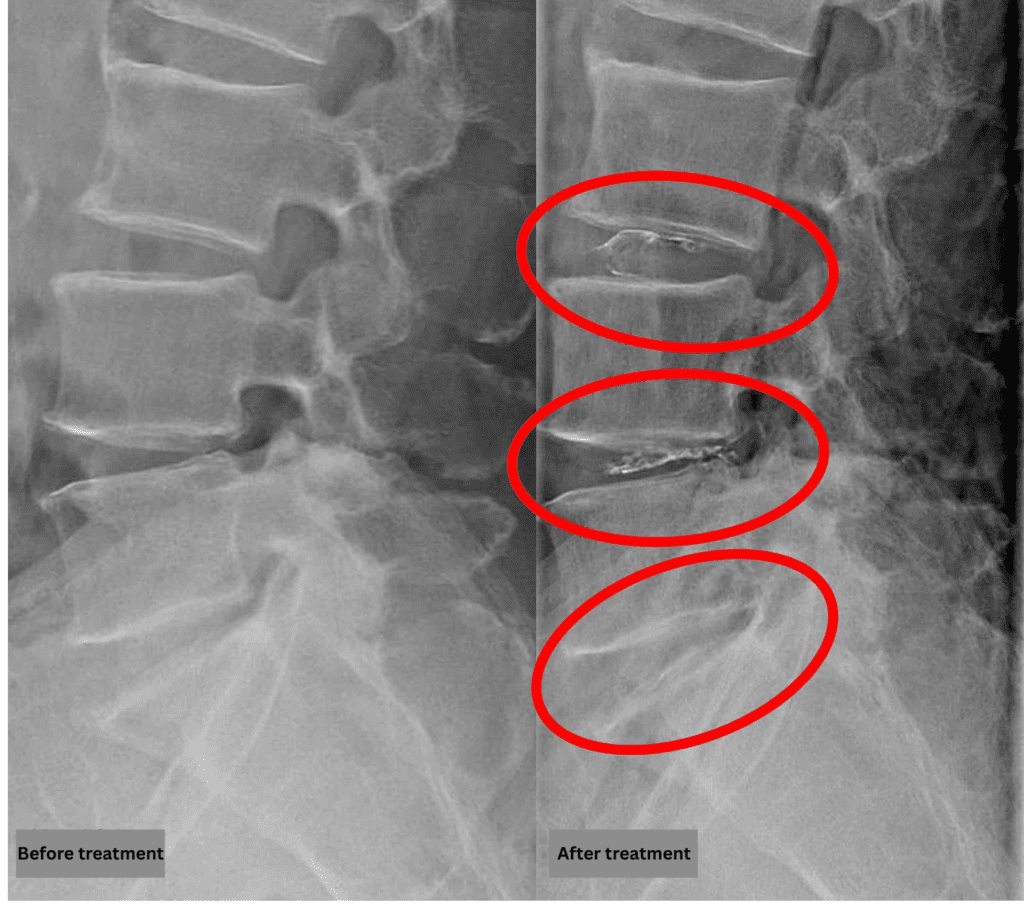

- L3/4, L4/5, L5/S1: Disc degeneration

The above findings were also observed on the imaging.

Compression of the spinal canal due to disc pathology at L3/4, L4/5, and L5/S1 is highly likely the cause of symptoms.

After consulting with the patient, the Cellgel Method was performed on L3/4, 4/5 and 5/s.